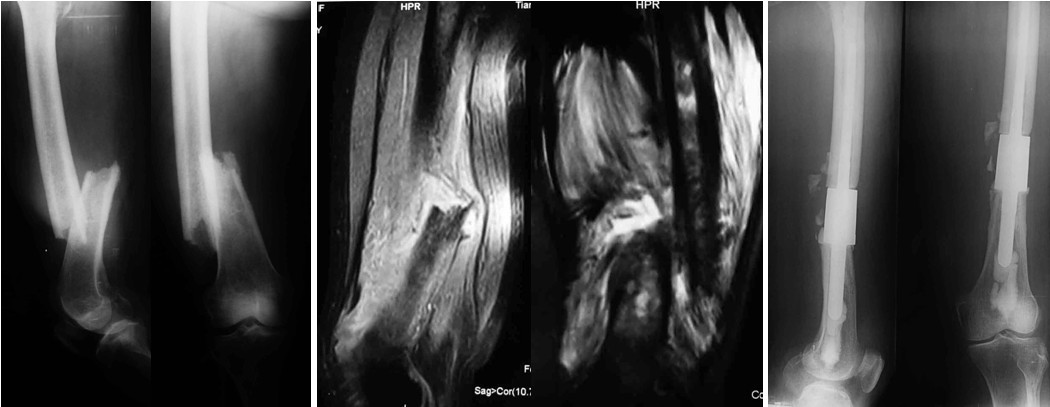

图2女,80岁,右股骨干转移瘤致病理性骨折,肿瘤段切除节段型人工假体重建